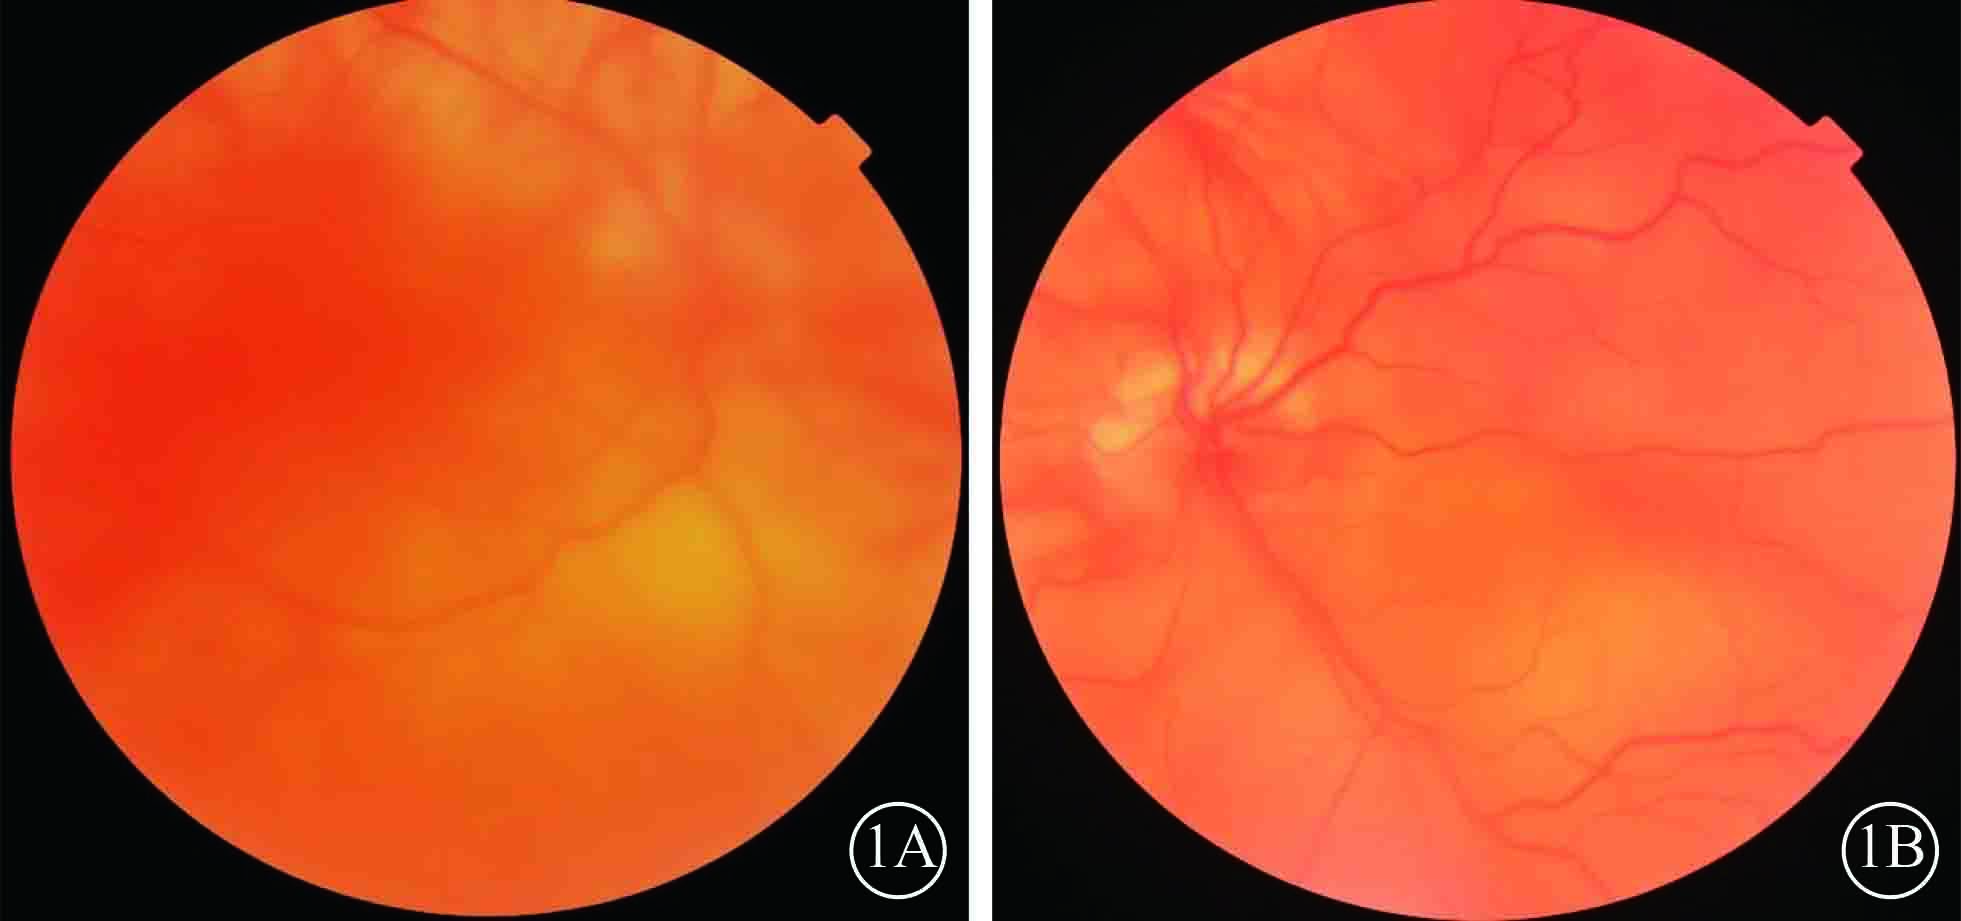

患者男,35歲。因體檢發現雙眼視網膜脫離1月余于2015年3月12日來我院眼科就診。患者自幼皮膚、毛發、虹膜無色素;雙眼視力差、畏光。否認外傷史、家族史。眼部檢查:右眼視力數指/30 cm,左眼視力0.1;雙眼矯正視力均無提高。雙眼眼瞼皮膚及睫毛均無色素;眼球水平震顫;角膜透明,瞳孔圓,虹膜半透明;晶狀體透明。雙眼眼底呈橙色。右眼全視網膜脫離,左眼0~8點時鐘位視網膜脫離(圖1);雙眼視網膜裂孔均窺不清。A型超聲檢查,右眼、左眼眼軸長度分別為26、28 mm。診斷:(1)雙眼孔源性視網膜脫離(疑似);(2)雙眼高度近視;(3)眼皮膚白化病。分別于2015年3月23日、5月11日行左眼、右眼視網膜復位手術。采用標準25G經睫狀體平坦部玻璃體切割手術。手術中見左眼視網膜裂孔分別位于 1、2、4、6點時鐘位,右眼裂孔位于8、11點時鐘位。先采用眼內電凝對裂孔邊緣進行標記,電凝處理后裂孔邊緣呈白色外觀(圖2);視網膜復位后,采用視網膜冷凍替代常規激光光凝對裂孔進行封閉;最后進行硅油眼內填充。雙眼均于手術后3個月行硅油取出手術。硅油取出后3個月,雙眼視網膜復位良好,眼底呈橙色,透見脈絡膜大血管(圖3);6個月,右眼視網膜復位良好,左眼下方視網膜再次脫離。于2016年2月1日再次行左眼視網膜復位手術、硅油填充。2016年12月27日隨訪,右眼視網膜復位良好;左眼硅油填充,下方視網膜仍有局部脫離(圖4)。

雙眼手術前彩色眼底像。1A. 右眼;1B. 左眼。眼底無色素,視網膜廣泛脫離

雙眼手術前彩色眼底像。1A. 右眼;1B. 左眼。眼底無色素,視網膜廣泛脫離

患者男,35歲。因體檢發現雙眼視網膜脫離1月余于2015年3月12日來我院眼科就診。患者自幼皮膚、毛發、虹膜無色素;雙眼視力差、畏光。否認外傷史、家族史。眼部檢查:右眼視力數指/30 cm,左眼視力0.1;雙眼矯正視力均無提高。雙眼眼瞼皮膚及睫毛均無色素;眼球水平震顫;角膜透明,瞳孔圓,虹膜半透明;晶狀體透明。雙眼眼底呈橙色。右眼全視網膜脫離,左眼0~8點時鐘位視網膜脫離(圖1);雙眼視網膜裂孔均窺不清。A型超聲檢查,右眼、左眼眼軸長度分別為26、28 mm。診斷:(1)雙眼孔源性視網膜脫離(疑似);(2)雙眼高度近視;(3)眼皮膚白化病。分別于2015年3月23日、5月11日行左眼、右眼視網膜復位手術。采用標準25G經睫狀體平坦部玻璃體切割手術。手術中見左眼視網膜裂孔分別位于 1、2、4、6點時鐘位,右眼裂孔位于8、11點時鐘位。先采用眼內電凝對裂孔邊緣進行標記,電凝處理后裂孔邊緣呈白色外觀(圖2);視網膜復位后,采用視網膜冷凍替代常規激光光凝對裂孔進行封閉;最后進行硅油眼內填充。雙眼均于手術后3個月行硅油取出手術。硅油取出后3個月,雙眼視網膜復位良好,眼底呈橙色,透見脈絡膜大血管(圖3);6個月,右眼視網膜復位良好,左眼下方視網膜再次脫離。于2016年2月1日再次行左眼視網膜復位手術、硅油填充。2016年12月27日隨訪,右眼視網膜復位良好;左眼硅油填充,下方視網膜仍有局部脫離(圖4)。

雙眼手術前彩色眼底像。1A. 右眼;1B. 左眼。眼底無色素,視網膜廣泛脫離

雙眼手術前彩色眼底像。1A. 右眼;1B. 左眼。眼底無色素,視網膜廣泛脫離